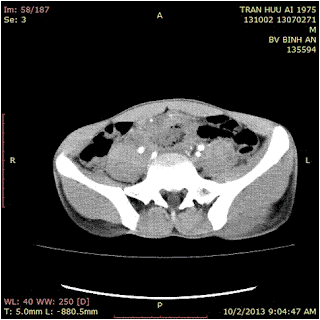

Later abdominal CT confirmed a right pelvic abscess with fecolith and a diagnosis of appendiceal abscess was made.\